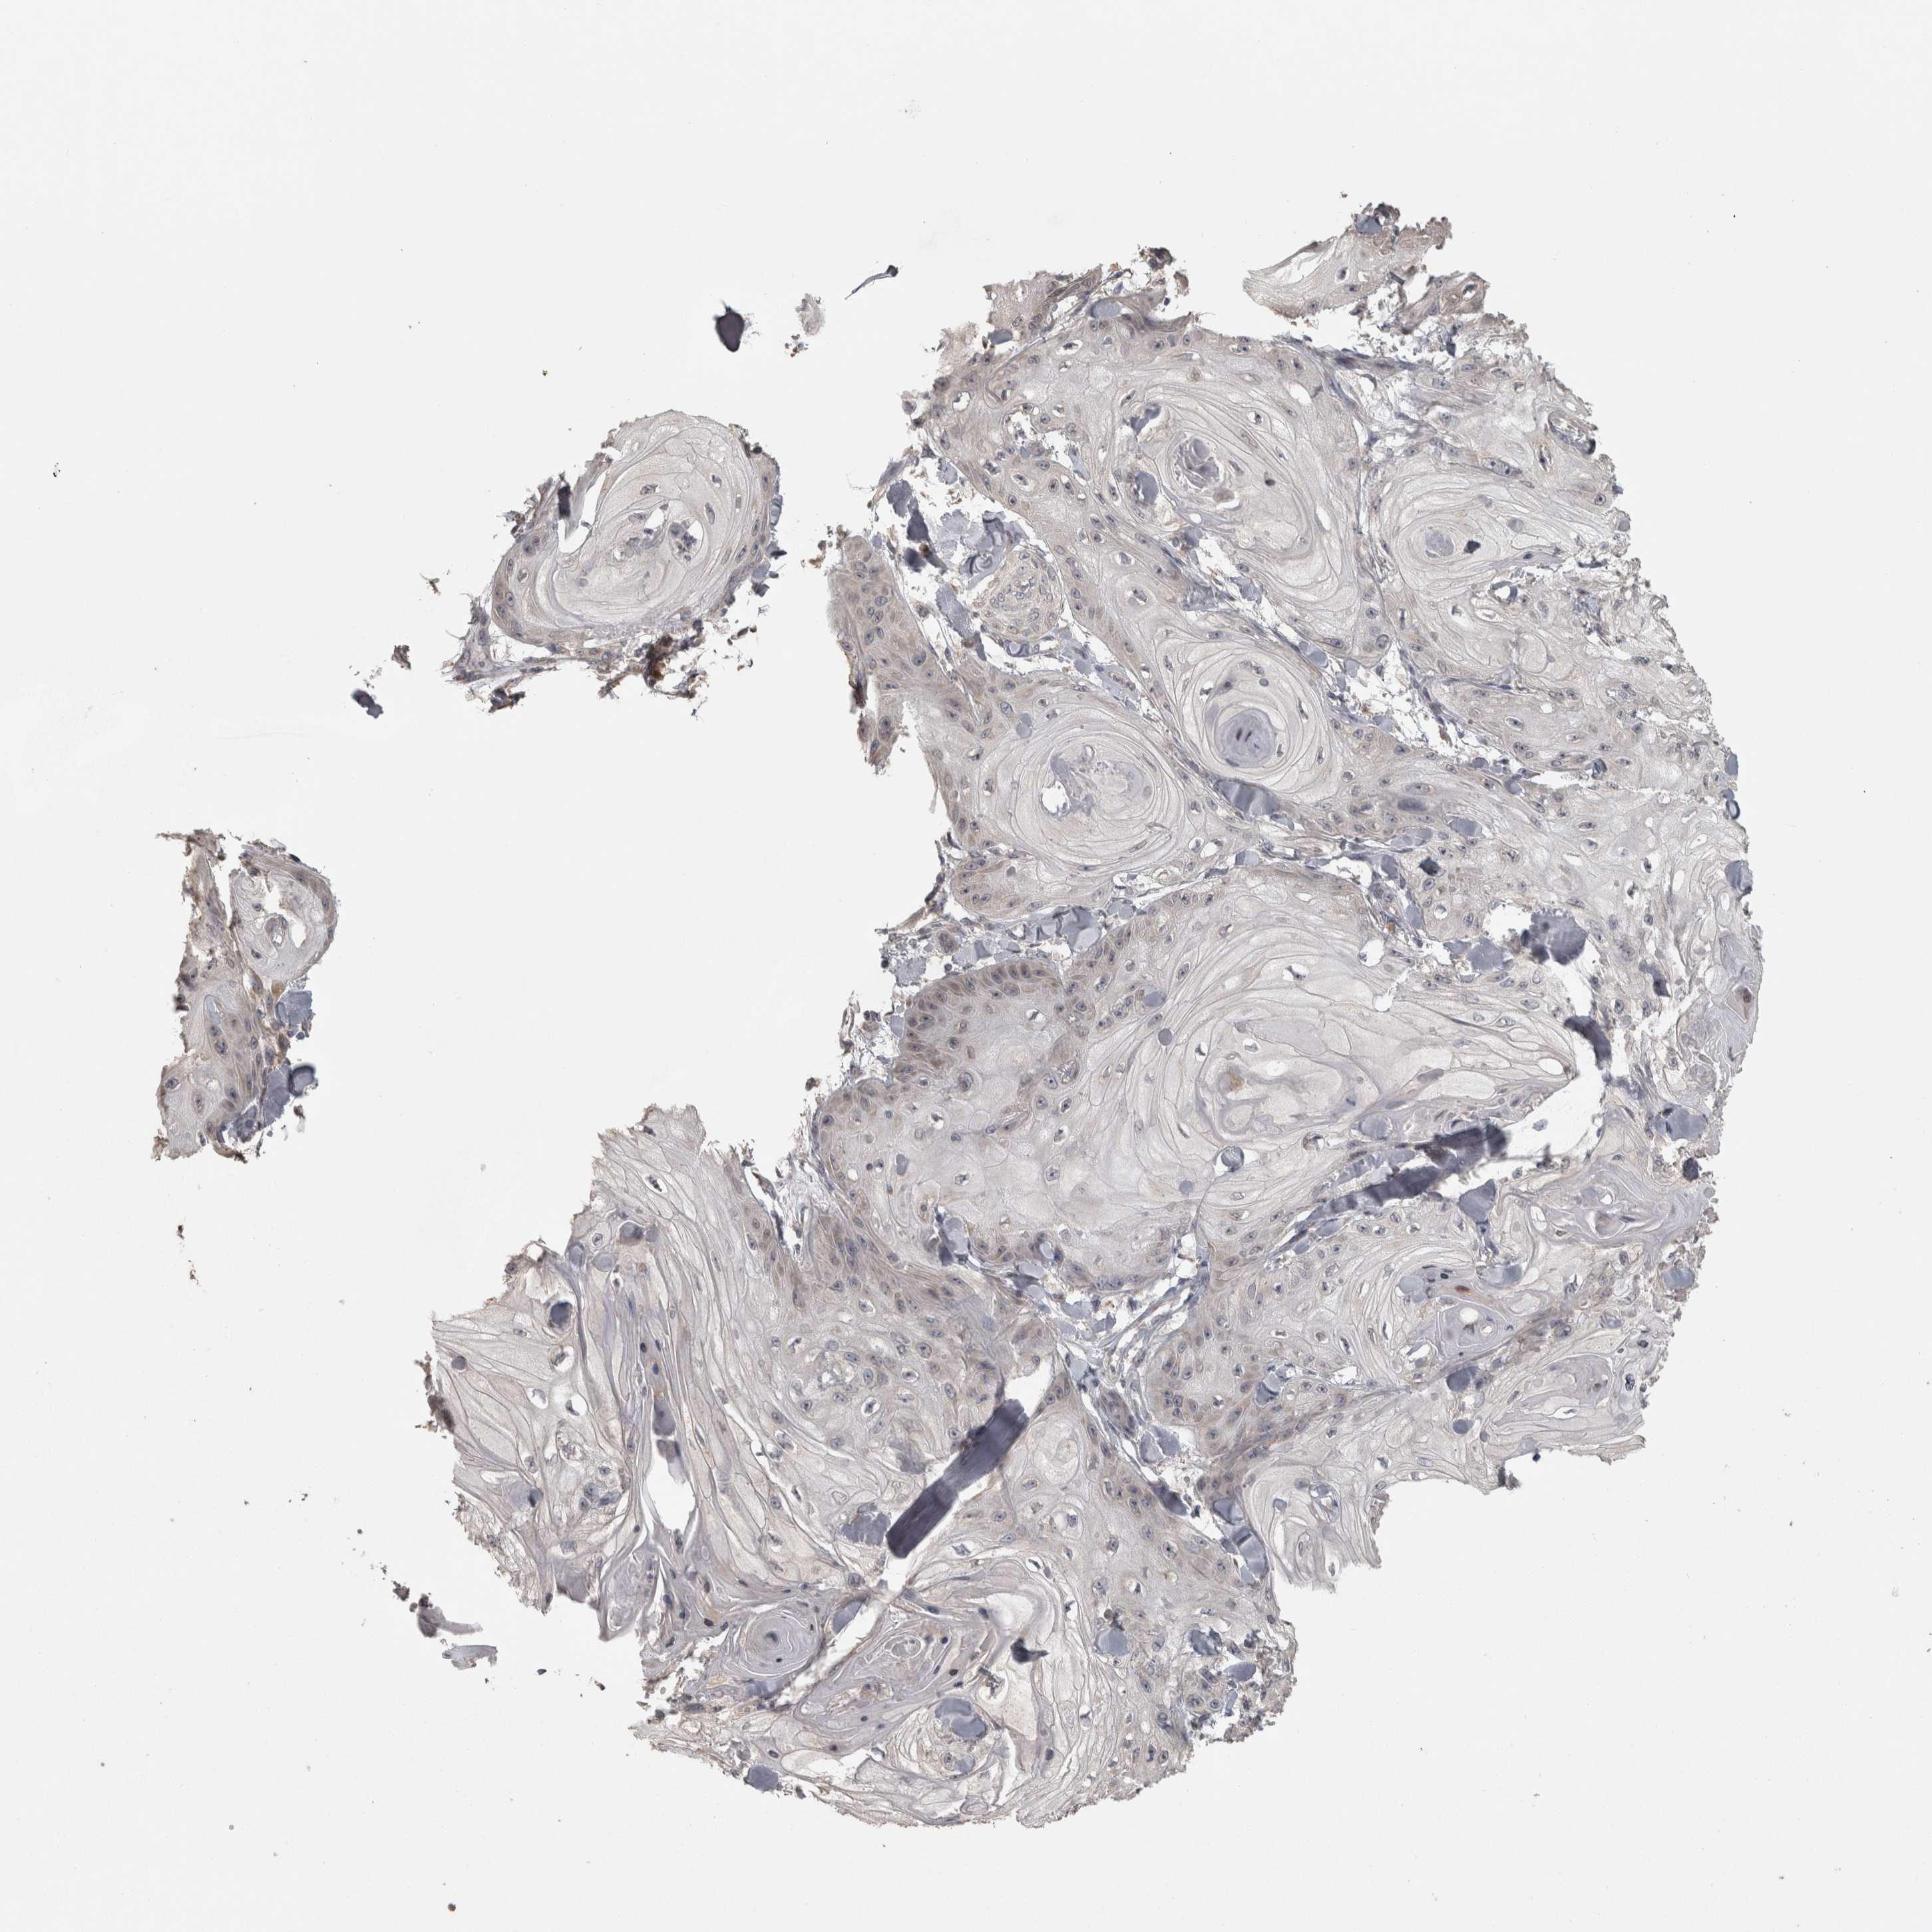

SKIN CANCER - Protein expressioni

A mouse-over function shows sample information and annotation data. Click on an image to view it in a full screen mode. Samples can be filtered based on level of antibody staining by selecting one or several of the following categories: high, medium, low and not detected. The assay and annotation is described here.

Each image is clickable and will lead to virtual microscopy that enables deeper exploration of all samples and also displays staining intensity scores, fraction scores and subcellular localization as well as patient and tissue information for each sample.

Antibody CAB020822

Low

Weak

<25%

Cytoplasmic/membranous

Squamous cell carcinoma, metastatic, NOS